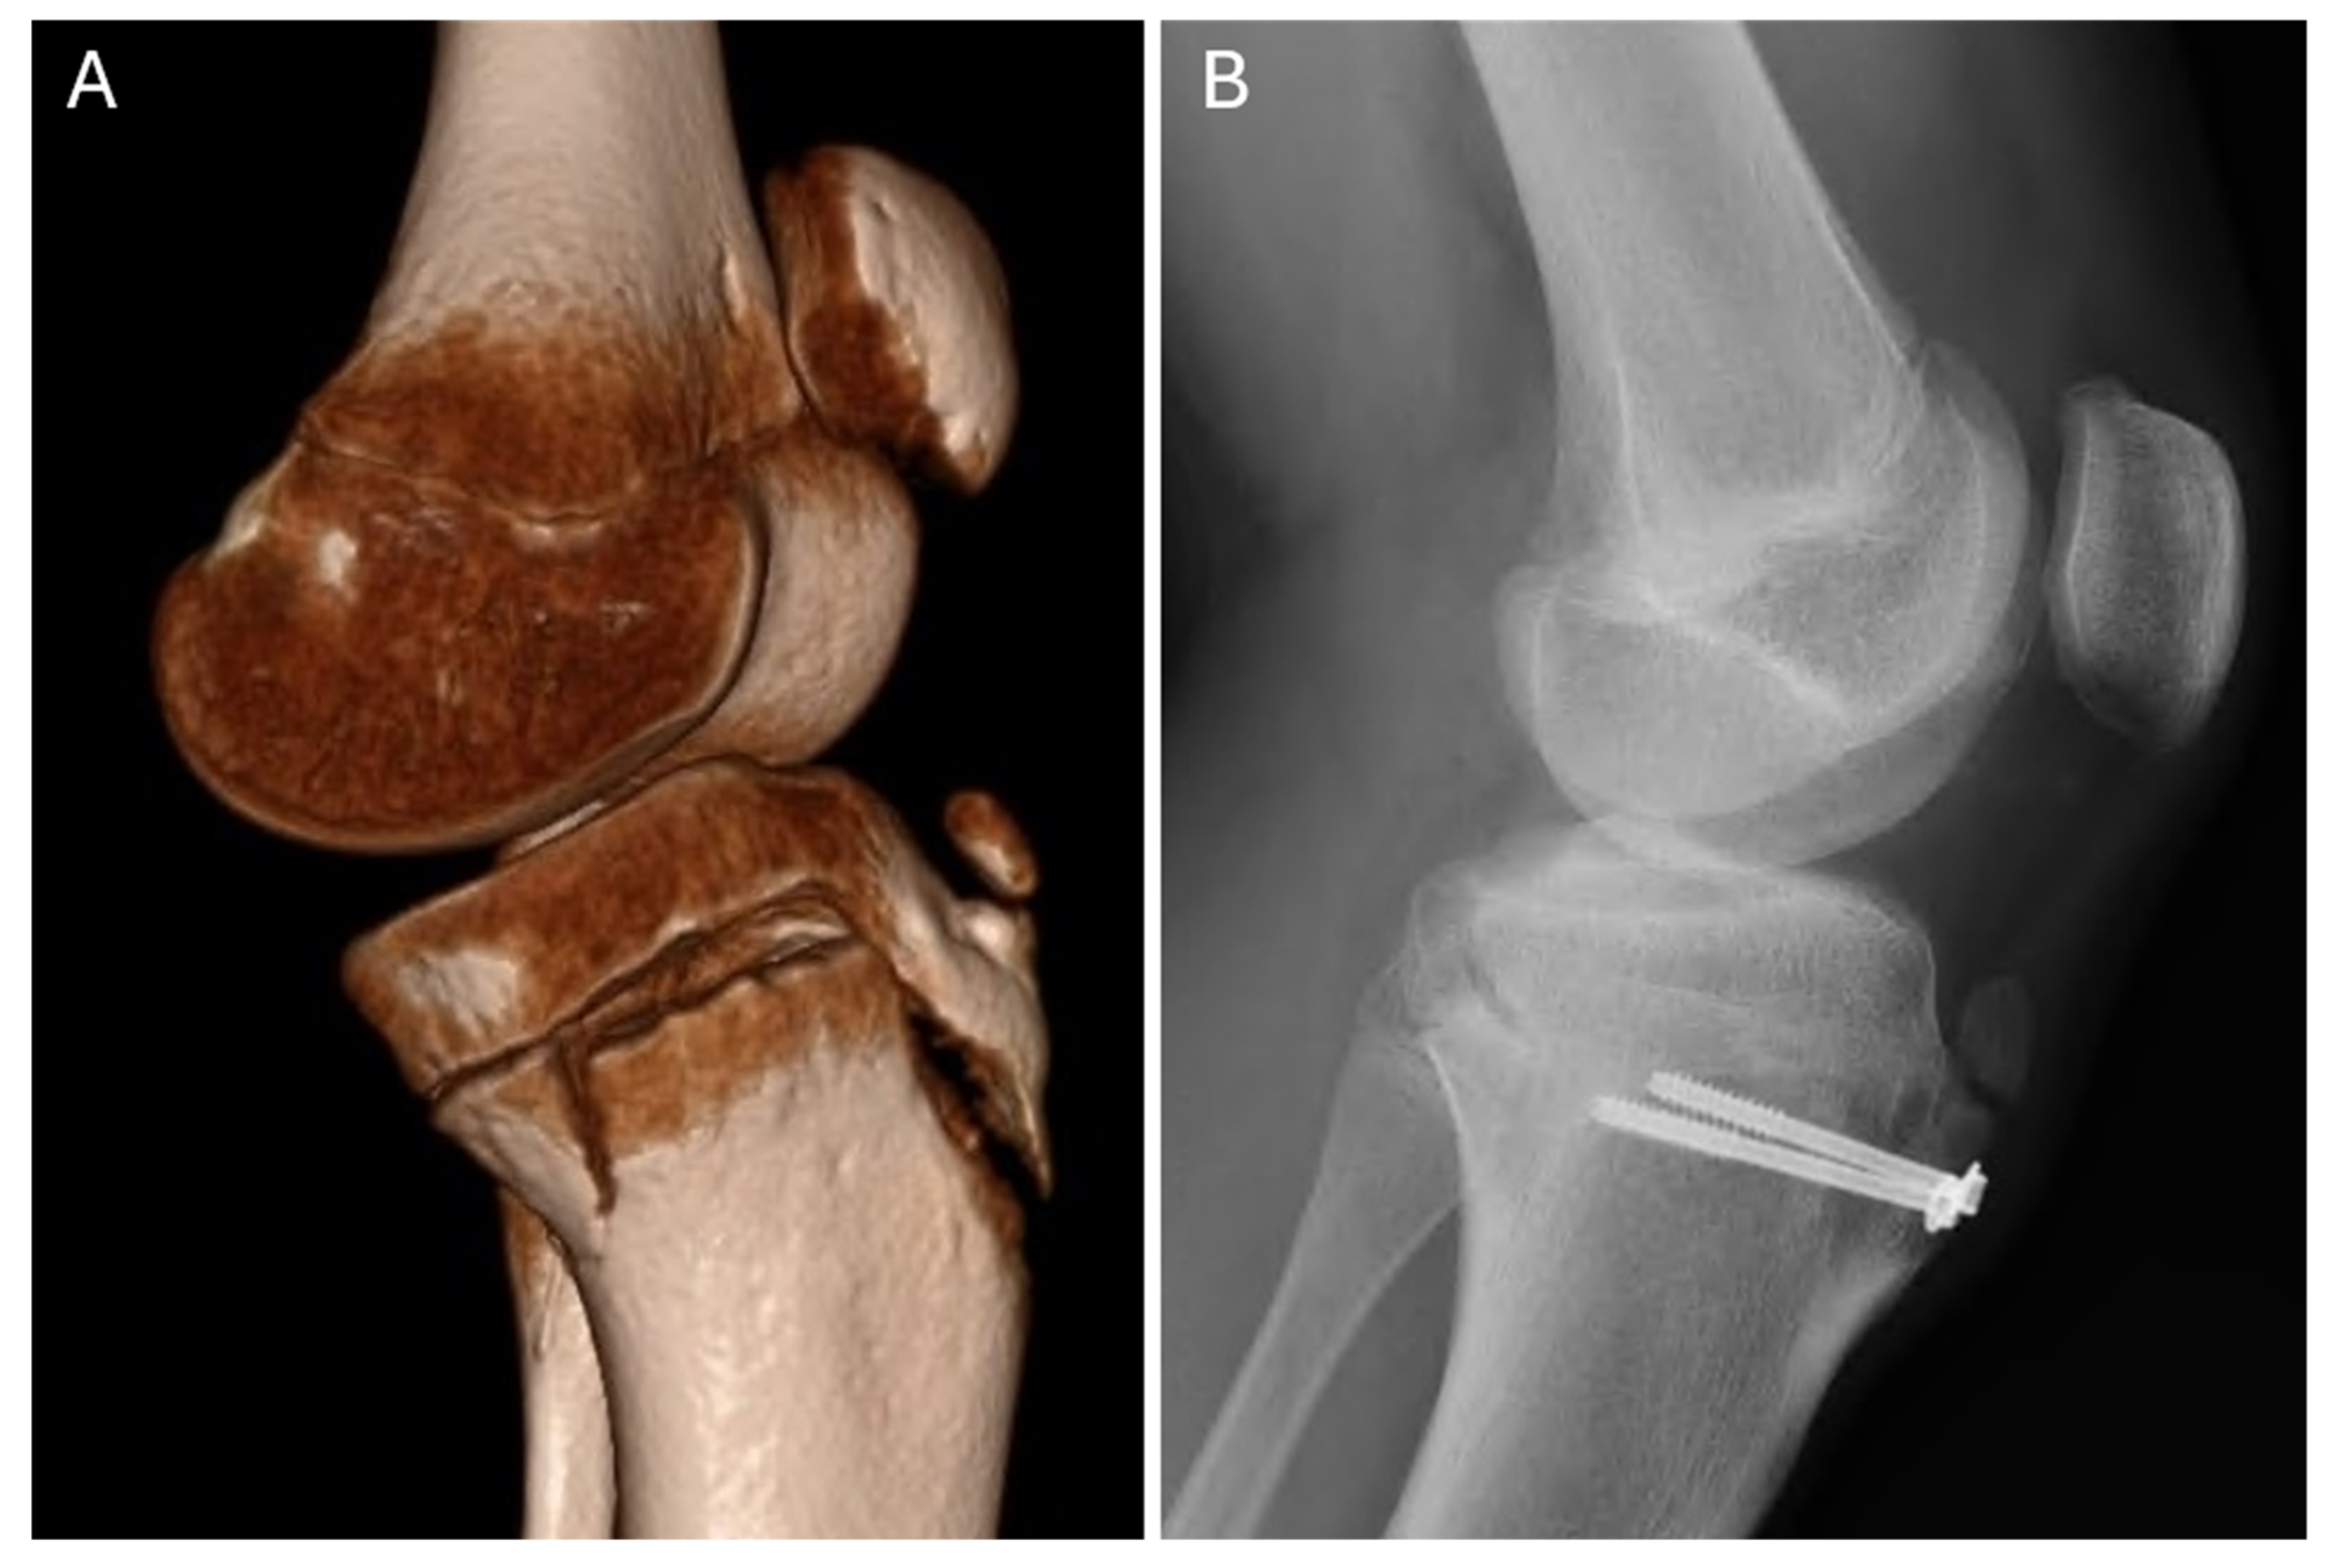

| 1 | Soccer | MRI, CT | Ib | ORIF | screws | patellar ligament | wound dehiscence | 10.8 |

| 5 | Handball | CT | IIIb | ORIF | screws | quadriceps tendon | intra-articular screw prominence | 10.7 |

| 9 | Soccer | CT | IVb | ORIF | screws | patellar ligament | - | 7.8 |

| 15 | Soccer | CT | IIb | ORIF | screws | patellar ligament | - | 10.0 |